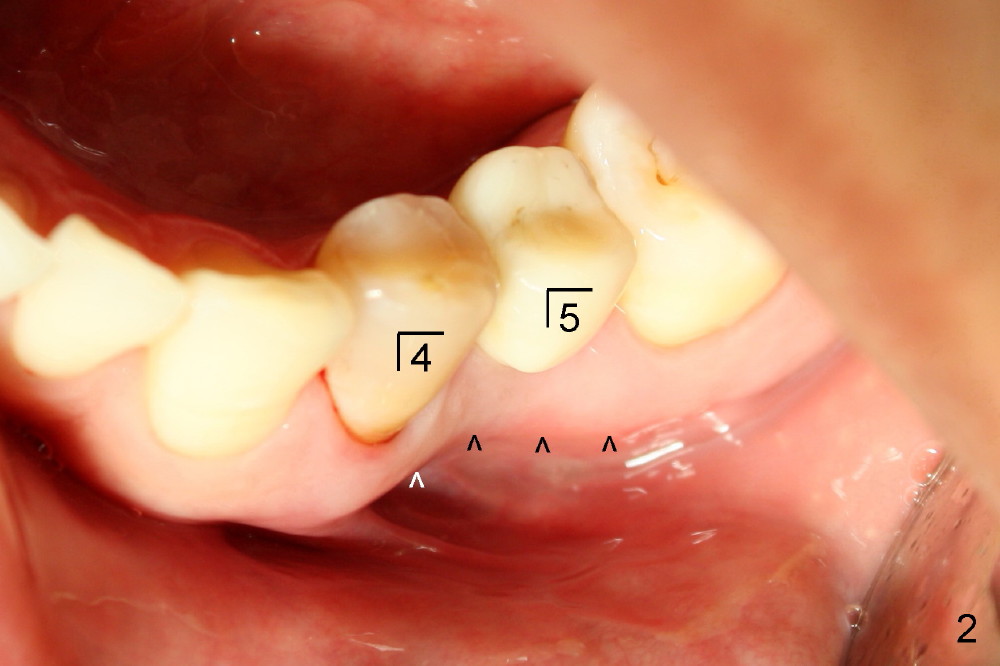

图一,二是治疗结束后两年拍摄的,其实右下第二双尖牙也作过根管治疗(图一),开口也由树脂修复(C),第一双尖牙在国内用银汞修复(A,没做根管治疗,所以牙齿没有变色)。图一,二最大不同的是右下第一双尖牙根部没有萎缩(图一*),而左下同样地方(植牙)明显凹陷(图二箭头),这可能说明尽管植牙,骨头还会萎缩。更准确地说萎缩是由于术前根尖病变所致,为了尽量减少这个趋势,拔牙后应该马上植牙,或者植骨。